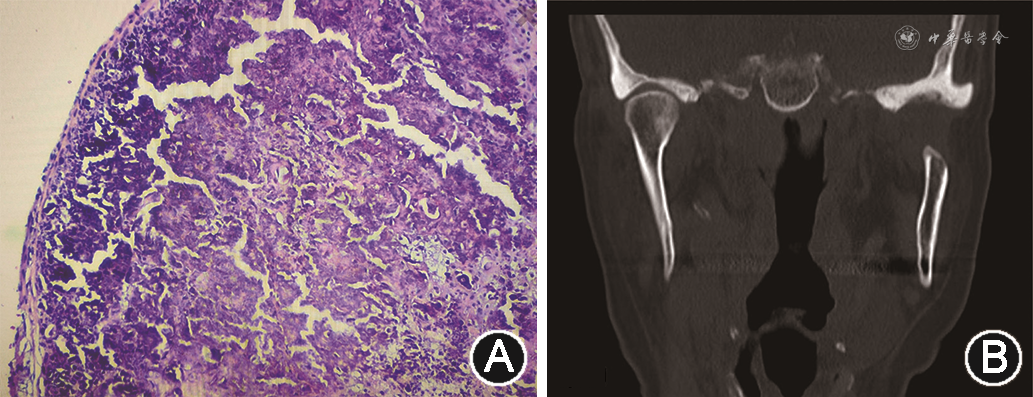

(5)治疗过程:见图2。术中做耳屏前及颞部切口,切开皮肤、皮下组织,依次分离帽状腱膜、颞浅筋膜、腮腺咬肌筋膜、颞深筋膜浅层,沿颧弓表面向下分离暴露肿物,见肿物包膜完整,因病灶累及髁突骨质,在计算机导航辅助下,于髁突颈部截断髁突,沿包膜外完整切除肿物及髁突。无菌生理盐水充分冲洗,以清除关节和周围组织的钙化碎片。充分止血冲洗后关闭术创。病理诊断为:左颞下颌关节区TC(图3A)。制动10 d后嘱患者进行张口练习。

(6)术后随访:术后随访7个月,患者恢复良好,左侧耳前区无疼痛、肿胀等不适症状,张口度恢复正常,开口偏左,咬合正常。无面神经损伤症状,无复发。CT检查示:左侧髁突呈术后缺损,截骨缘光整,周围软组织界面尚清晰(图3B)。

组织学检查是诊断TC的金标准。大体标本通常为致密或不规则破碎的纤维囊壁包裹的肿物,质地橡皮样,切面见致密的纤维组织网,内含灰黄色钙质和白色糊状、石灰状液体,触之有沙粒感。镜下TC的组织学表现分为活动期和非活动期,两者也可同时存在,其中活动期更常见,也更易识别。它的特点是中央有一个大的钙化颗粒状区域,周围是炎症浸润,主要是上皮样组织细胞,混合有淋巴细胞、分散的单核或多核巨噬细胞。非活动期只观察到钙化沉积物和致密的胶原组织,无炎症细胞浸润[14, 15]。